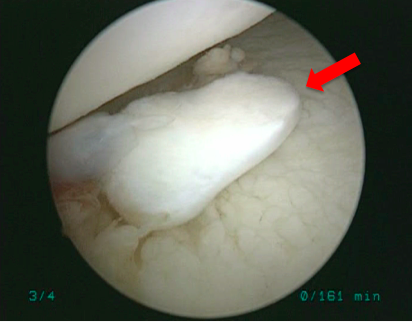

手術所見

| 遊離体 | 遊離体摘出時 |

![]()  |

現病歴:ソフトテニス中に右肩関節を外転外旋位でボールを打ち返した歳に脱臼感が出現しました。佐久平整形外科クリニック受診し右肩関節唇損傷の疑いで3ヶ月間リハビリテーションを行いましたが、症状改善なく造影MRI検査施行し、結果より前方関節唇損傷・骨性Bankart病変と診断されました。疼痛・脱臼感などの症状改善がみられず競技継続を希望されたため、鏡視下肩関節唇形成術を施行し、その術中で遊離体を発見したため摘出術も施行しました。